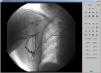

El Servicio de Cirugía Cardíaca y Anestesia contraindican el implante de marcapasos epicárdico, por alto riesgo quirúrgico. Se procede al implante de marcapasos definitivo bicameral por vía femoral derecha con electrodos de fijación activa de 85cm. Este se lleva a cabo satisfactoriamente, sin incidencias (figs. 1 y 2).